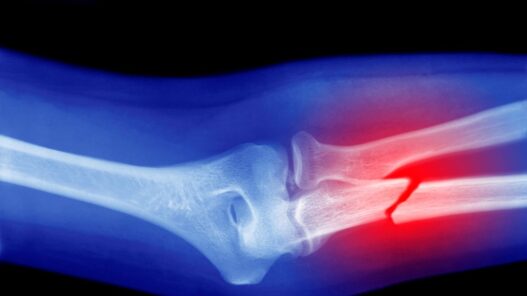

Por su parte, la revisión de estudios in vivo constató que la acumulación de microplásticos en el organismo disminuye el recuento de glóbulos blancos, lo que sugiere alteraciones en la función de la médula ósea. Además, se observó que la aceleración del envejecimiento inducida por los osteoclastos puede asociarse con el deterioro de la microestructura ósea y con displasias, lo que incrementa el riesgo de fragilidad, deformidades e incluso fracturas patológicas.

“A pesar de que las enfermedades osteometabólicas están relativamente bien comprendidas, existe una laguna respecto a la influencia de los microplásticos en su desarrollo. Por ello, uno de nuestros objetivos es generar evidencias que demuestren que estos contaminantes podrían constituir una causa ambiental, y potencialmente controlable, que ayude a explicar, por ejemplo, el aumento proyectado de fracturas óseas”, adelantó Oliveira.